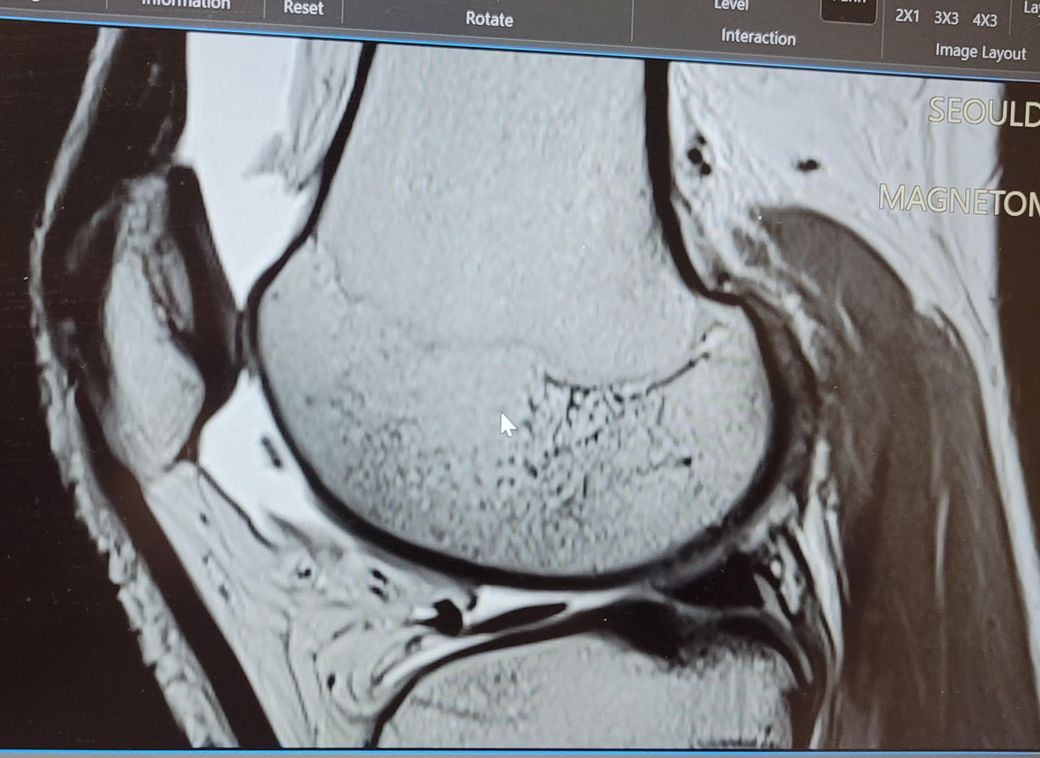

왼쪽 무릎 MRI 사진인데요

ICRS 몇등급 정도일까요?

판독지에 별다른 말이 없어서요ㅠ

오른무릎 활차구 연골 결손 MRI 사진입니다

• 1번 째 사진

첨부하신 MRI 영상에서는 활차구의 연골 표면이 다소 불규칙하게 보이지만, 연골이 완전히 벗겨졌거나, 연골 아래 뼈가 드러나는 심한 손상은 명확하게 보이지 않습니다. 이러한 소견은 일반적으로 ICRS 분류상 2등급에 가까울 가능성이 있습니다. ICRS 2등급은 연골 표면에 결손이 있으나 깊이가 얕고, 연골하골까지 손상이 이르지는 않은 상태를 의미합니다.

다만 MRI만으로 정확한 등급을 단정하긴 어렵고, 실제 관절내시경과 같은 직접적인 확인을 통해 보다 정확한 진단이 가능합니다. 영상 해석은 촬영 각도, 기기 해상도, 해석자의 경험 등에 따라 달라질 수 있어, 세부적인 내용은 영상의학과나 정형외과 전문의와 직접 상담을 받으시는 것이 가장 안전합니다.